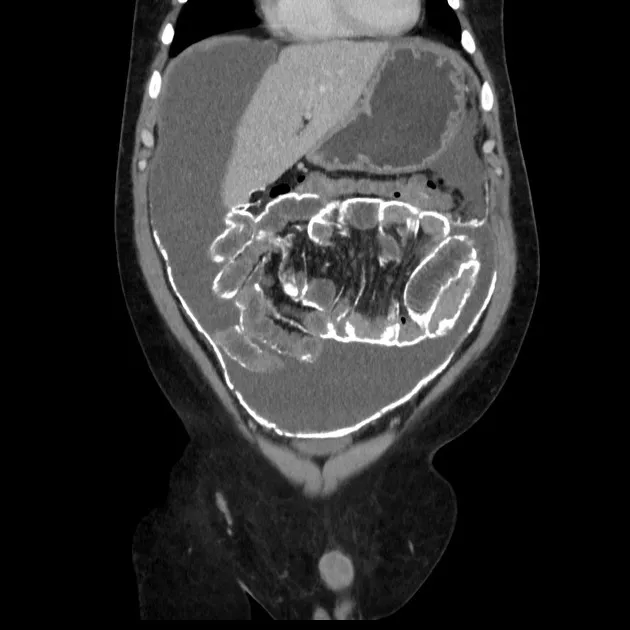

nefrolitiase